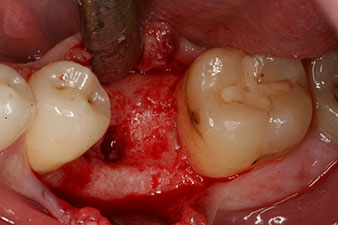

Fig. 2: Six weeks later there was an incompletely ossified alveolus in the region of the mesial root.

However, six weeks after the extraction incomplete ossification was found after preparation of the mucoperiosteal flap in the region of the former mesial alveolus.

The implant was placed as planned after thorough removal of the granulation tissue (blueSky, bredent).